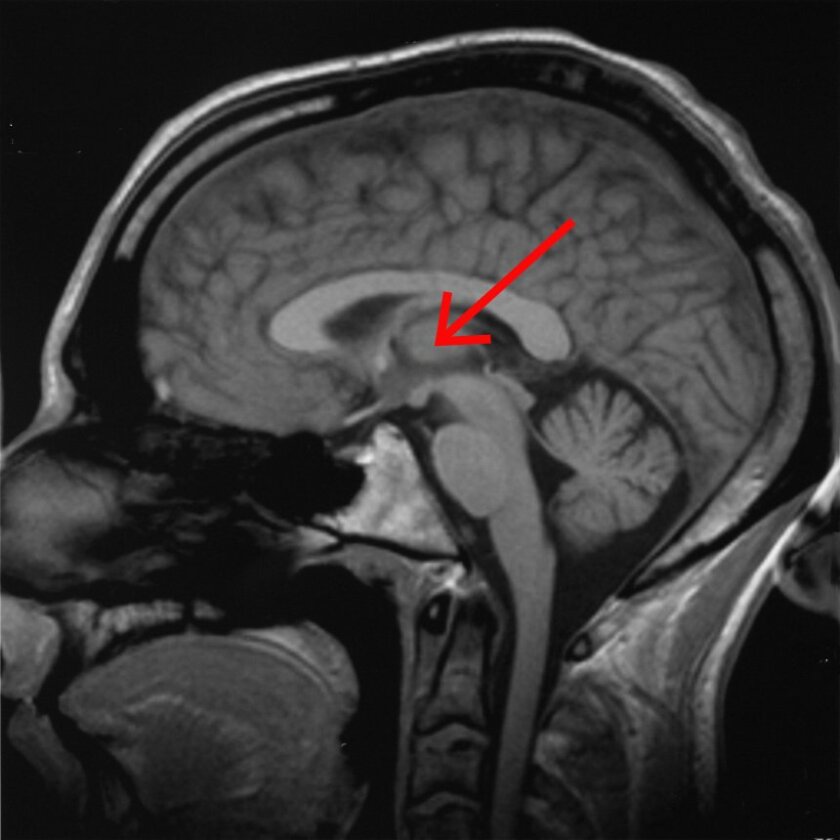

Scientists have long been studying the thalamus, which sits deep in the brain near the brain stem, to learn what role it plays in sleep, waking, consciousness and alertness. But this research, in which targeted electrical stimulation was applied to a specific area, narrowed the search down further than ever before. The electrodes used in the study were more tailored to the shape of the brain structures they were designed to work on, and the electrical stimulation was designed to mimic the activity of a normal, waking brain.

The central lateral thalamus is found deep in the center of the brain, close to the brain stem AxelBoldt/Wikimedia Commons